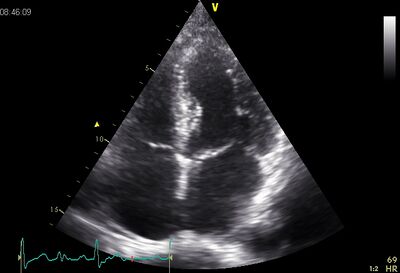

Echocardiographic views

Plax TV02.jpg Psax ao.jpg

Plax by tilted PSax Ao